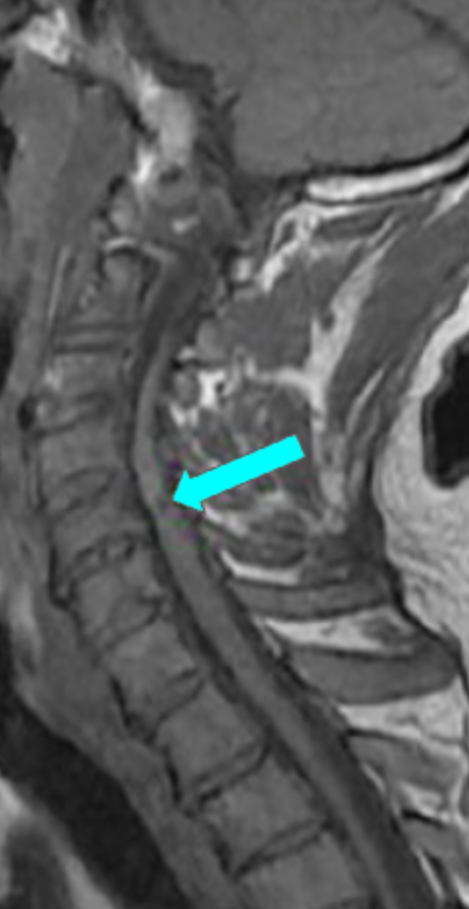

T1 hypointensity refers to focal or diffuse low signal intensity within the cervical spinal cord on T1-weighted MRI. When present, it is considered a marker of chronic spinal cord injury, most commonly representing myelomalacia, cord atrophy, gliosis, or irreversible ischemic damage.

In the context of cervical spinal stenosis or degenerative cervical myelopathy (DCM), T1 hypointensity is associated with longstanding compression, advanced disease, and poorer neurologic recovery compared with patients who demonstrate T2 hyperintensity alone.

• Chronic cord injury: Focal T1 hypointensity; suggests early myelomalacia

• Advanced chronic myelopathy: Diffuse or multilevel T1 hypointensity; cord atrophy

• T1 hypointensity is always pathologic

• Indicates irreversible spinal cord damage in most cases

• Strongly associated with poor postoperative neurologic recovery